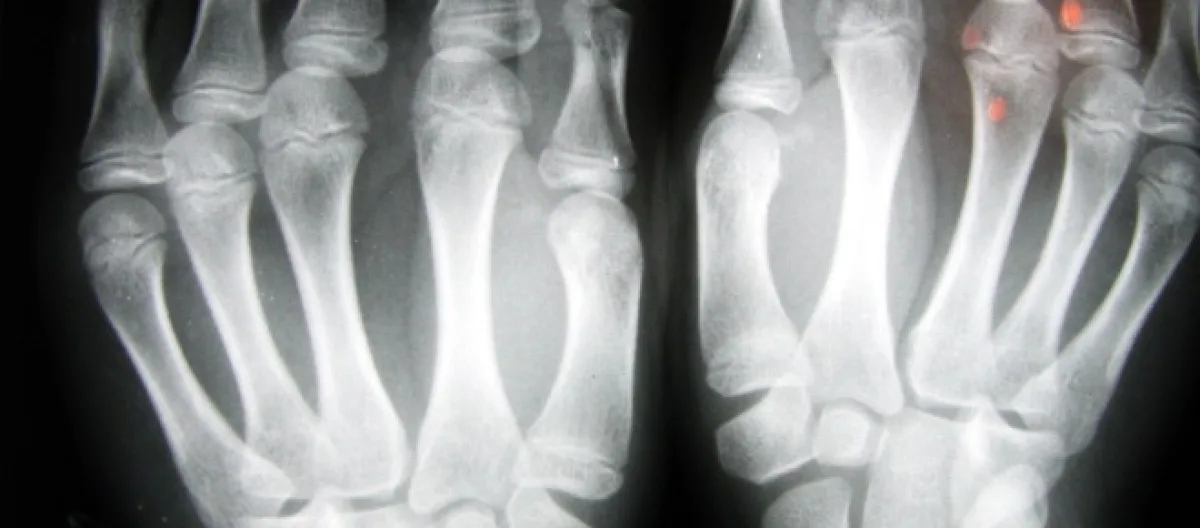

Los síntomas del cáncer de hueso incluyen dolor dentro de los huesos, que puede confundirse con artritis. Sin embargo, también hay otros tres síntomas.

Los síntomas del cáncer de hueso ocurren en las áreas afectadas, que generalmente son los huesos largos de las piernas y la parte superior de los brazos.

• El síntoma más común del cáncer es el dolor en los huesos, que empeora gradualmente.

Los síntomas del cáncer de hueso se desencadenan por la actividad de las células cancerosas que alteran el hueso.

El cáncer puede aparecer en cualquier hueso del cuerpo, aunque es más común en los huesos largos de las piernas y la parte superior de los brazos.

Los síntomas del cáncer de hueso, incluido el principal signo de dolor óseo, a veces pueden confundirse "erróneamente" con la artritis. El cáncer de hueso es un tipo raro de cáncer que comienza en los huesos.

El síntoma principal de esta clase de cáncer es el dolor en los huesos que no desaparece, pero empeora con el tiempo. Es posible que tenga un área dolorosa o sensible. Puede ser doloroso cuando estás descansando. El dolor a menudo empeora cuando estás en la cama por la noche.